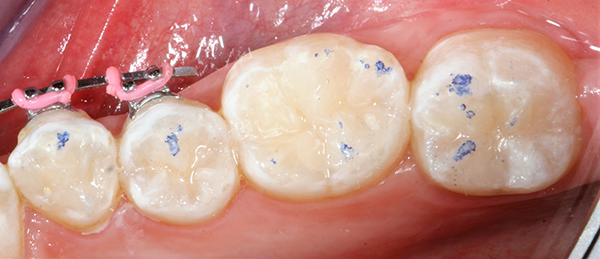

Occlusion was checked with articulating paper (AccuFilm®, Parkell) (Fig. 7) and adjusted as needed with a finishing bur (Fig. 8).

Fig. 7 Fig. 8

As one can observe from the pictures, when anatomy is closely followed in the reconstruction of the missing tooth structure, necessary occlusal adjustment is very minimal.